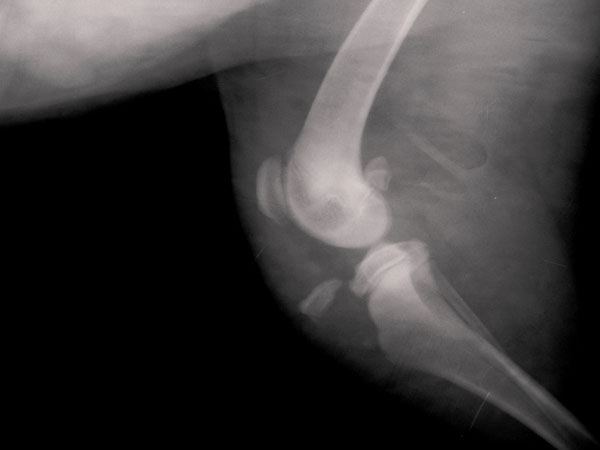

Ροτβάιλερ 5 μηνών με αποσπαστικό κάταγμα κνημιαίου κυρτώματος.

Φωτογραφίες πρίν και μετά το χειρουργείο.

Rottweiller θηλυκό 4-5 μηνών με αποσπαστικό κάταγμα κνημιαίου κυρτώματος αριστερού οπίσθιου άκρου προ 2 ημερών.